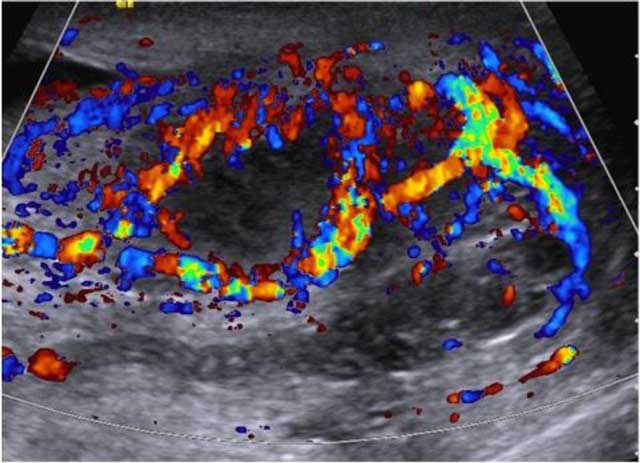

Figure 3

Longitudinal color Doppler image shows hypoechoic abscess of the hilum extending to the epididymis with increased flow signals in peripheral portion.